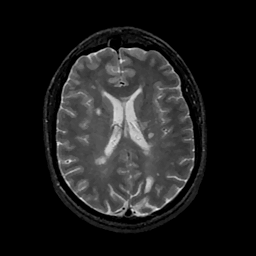

MR Study #11, May 5, 1991 -- Slice #30